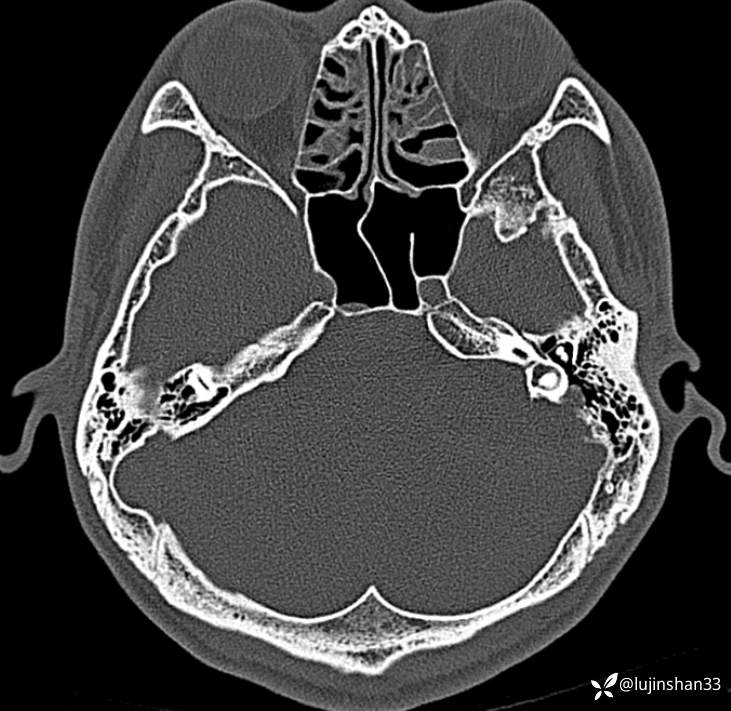

首次术前CT: